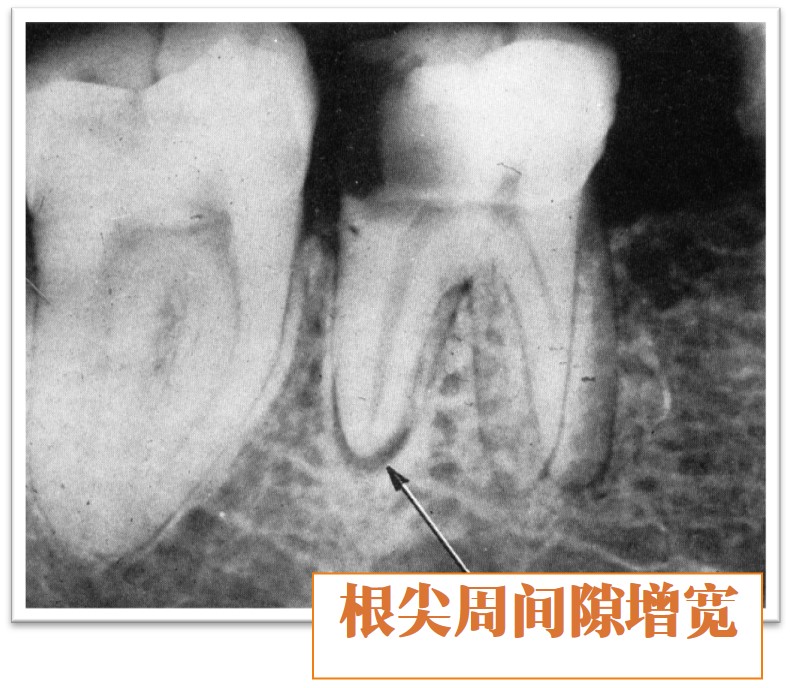

5、X线片显示,根尖周间隙增宽(图9.1-2),硬骨板不清晰,长期病变有骨吸收。

图9.1-2 根尖周间隙增宽